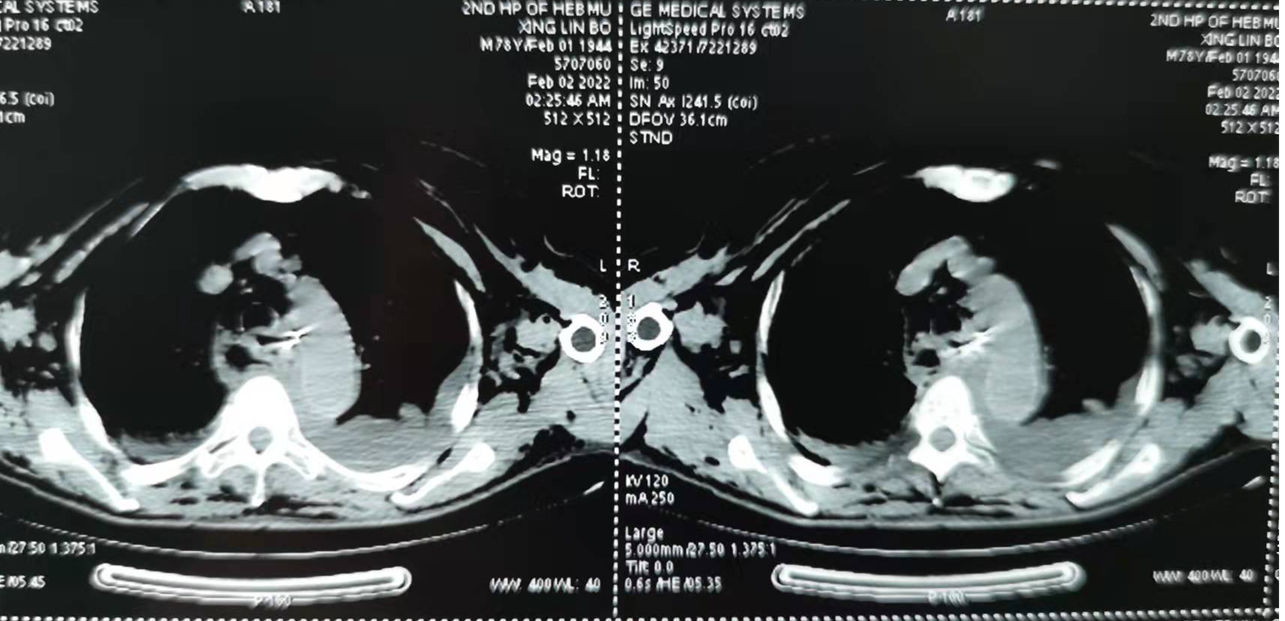

我院成功救治一例高龄食管异物穿孔并纵隔感染患者 关键字:胸外科 近日,我院胸外科与消化内科、麻醉科、手术室、急诊ICU精诚合作,成功治疗一例食管异物伴感染,同时合并...